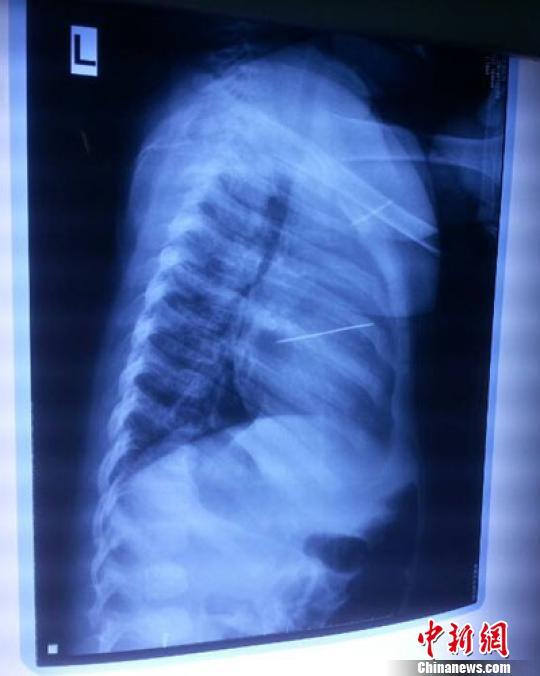

女嬰胸片提示心臟里面扎了一個(gè)縫衣針 蔡迅翔 攝

醫(yī)院胸心外科主任翟波介紹說(shuō),1月22日,小患者彤彤因?yàn)榘l(fā)燒抽搐來(lái)醫(yī)院就診,常規(guī)檢查時(shí)發(fā)現(xiàn)孩子心臟里面扎了一個(gè)縫衣針。

“第二天上午,我們做了個(gè)緊急彩超檢查,發(fā)現(xiàn)針是從患者右心室表面刺入,穿破室間隔,到達(dá)左心房,中間還有一部分損害到二尖瓣。于23號(hào)下午,我們就做了一個(gè)緊急手術(shù),手術(shù)中發(fā)現(xiàn),這枚針已經(jīng)刺入心臟,沒(méi)入了右心室的下面,表面已經(jīng)看不到針了,僅能看到一個(gè)小針眼,還在往外滲血,一點(diǎn)一點(diǎn)的滲,心包腔里面大概有100多毫升的出血,心包上一個(gè)洞,針在右心室表面刺入以后,穿過(guò)室間隔,在二尖瓣的上方,進(jìn)入了左心房,在針的四周,有很多纖維沉積物,包繞著這枚針?!钡圆ㄕf(shuō),他們把針取出來(lái)以后,測(cè)量了一下,長(zhǎng)度大概是五厘米,同時(shí)發(fā)現(xiàn)這個(gè)針給患者左心房的后壁造成了一定的損傷,左心房的后壁已經(jīng)損傷了三分之二,還剩下有左心房的外膜,很薄的一層,如果這一層再破的話,這個(gè)孩子將會(huì)引起大出血,很快就會(huì)死亡。